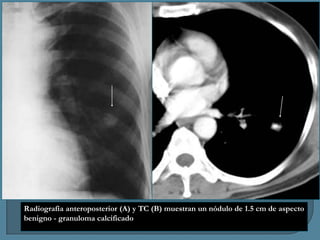

Radiografía anteroposterior (A) y TC (B) muestran un nódulo de 1.5 cm de aspecto

benigno - granuloma calcificado